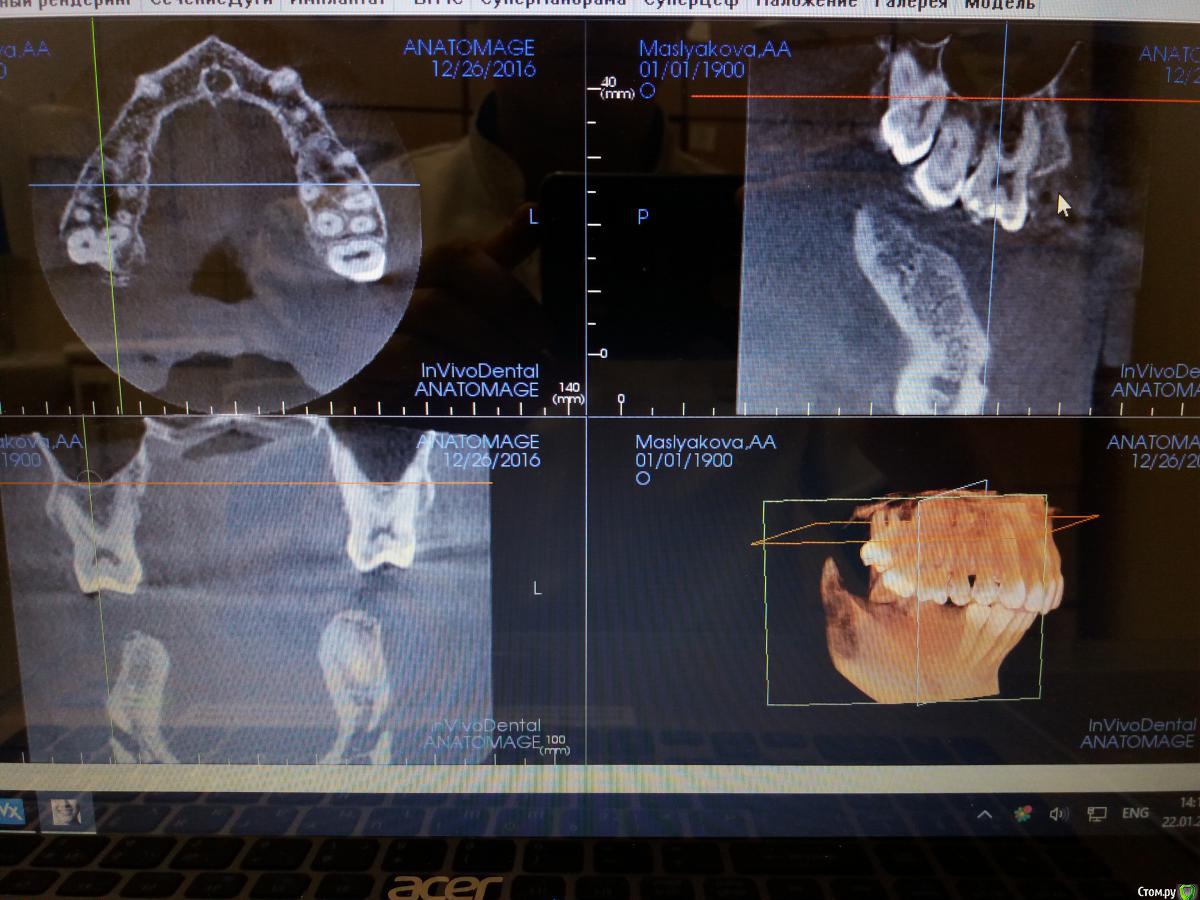

azerty Опубликовано 19 января, 2017 Поделиться Опубликовано 19 января, 2017 Что бы не плодить темы, подскажите коллеги,возможна ли интрузия моляров на верхней челюсти при очень близком расположении корней рядом с гайморовой пазухой?Не произойдет ли перфорация дна пазухи?Снимки прикреплю завтра,спасибо! Ссылка на комментарий

Opdihatop Опубликовано 22 января, 2017 Поделиться Опубликовано 22 января, 2017 Перфорации не будет скорее всего (особенно, если силы давать небольшие), но и интрузия идти будет очень медленно. Ссылка на комментарий

orthophil Опубликовано 6 февраля, 2017 Поделиться Опубликовано 6 февраля, 2017 Господа! О какой перфорации вообще идет речь. Моляры же не молотком вколачивать придется. А вот расстояние между верхушками и гайморовой пазухой уменьшится. Ссылка на комментарий